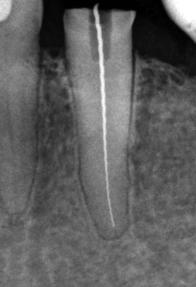

perfekte Wurzelkanalfüllung